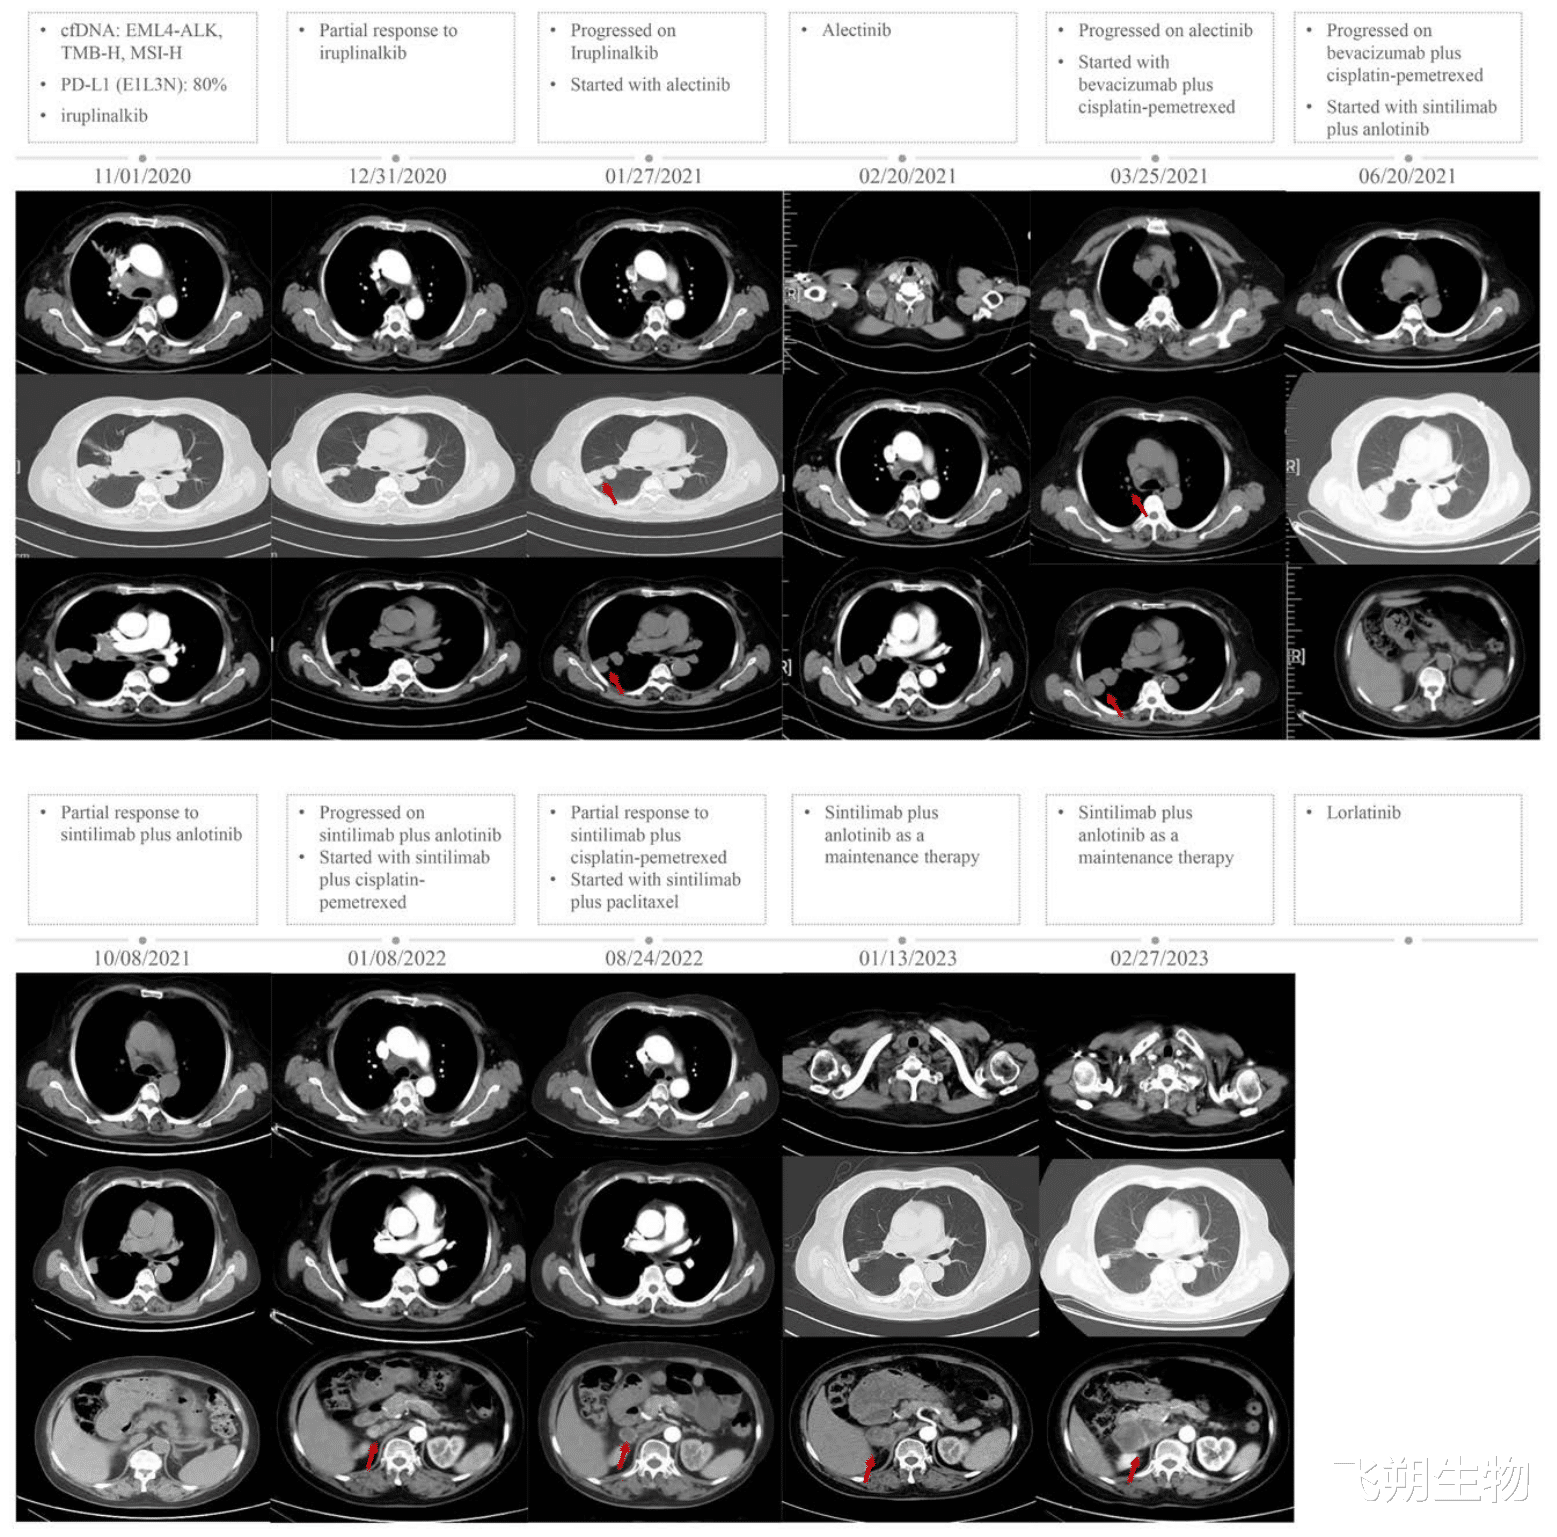

患者于2020年11月1日开始接受伊鲁阿克一线治疗。2020年12月首次随访CT显示部分缓解。2021年1月27日,CT显示右上肺及右侧气管旁淋巴结肿物增大,随后患者接受阿来替尼二线治疗。在接下来的2个月内疾病进展,右上肺肿物持续增大,纵隔淋巴结肿大。ALK-TKIs治疗失败后(3月25日),患者接受了顺铂、培美曲塞联合贝伐单抗治疗。6月20日的CT显示右上肺肿物增大,纵隔和右侧锁骨淋巴结肿大,右侧肾上腺发现新病灶。6月28日,患者接受了8个周期的信迪利单抗(200 mg)联合安罗替尼(10 mg)四线治疗。期间影像学显示病情改善,右上肺和右侧肾上腺病灶缩小。

2022年1月26日,CT显示右侧肾上腺结节增大,同时右侧颈部肿块增大伴有疼痛。对右侧颈部肿块行穿刺活检进行病理评价和NGS分析,使用22C3抗体检测PD-L1显示TPS为10%。NGS结果与2020年10月16日的结果一致,检出EML4-ALK融合(E13:E20),TMB-H和MSI-H。2月25日,临床团队改变了治疗方案,使用4个周期的信迪利单抗200 mg联合白蛋白紫杉醇400 mg加卡铂500 mg,作为五线治疗。此外,2022年3月14日至4月24日,患者接受了60 Gy/30 fx的右侧锁骨上放疗。6月15日的CT发现部分反应,右肺肿块、纵隔和锁骨上淋巴结病灶有所改善。8月24日,患者接受了信迪利单抗联合白蛋白-紫杉醇治疗,一个周期后患者出现低钠血症、骨髓抑制、甲状腺功能减退等不良事件,经强的松和甲状腺素治疗后好转。由于对化疗不耐受,患者于10月31日继续使用信迪利单抗联合安罗替尼作为维持治疗。

2023年3月13日,患者接受了95% PTV, 40 Gy/20 fx的右侧肾上腺放疗,随后疾病再次进展。8月14日,右侧颈部肿块穿刺活检的NGS检测显示EML4-ALK(11.13%)、STK11突变(36.9%),TMB-H(82.74突变/Mb)和MSI-H状态。使用22C3抗体检测PD-L1显示TPS为60%。在以ICB为基础的治疗进展后,患者接受洛拉替尼治疗,仍在随访中,总生存期超过3年。